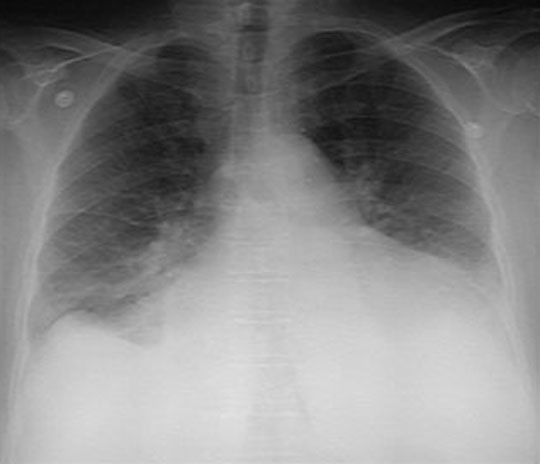

CXR

Pulmonary embolism-heart failure-lung/micro  Dr Ralph Leischner